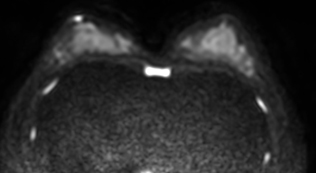

無痛乳房MRI

DWIBSとは:水分子の動きを画像化し、がん細胞を白く浮かび上がらせる技術。

乳腺MRIへの応用:「ドゥイブス・サーチ」と呼ばれ、乳房を圧迫せず痛みなく検査可能。放射線被ばくゼロ、造影剤不要。

精度:マンモグラフィよりも高感度で、特にデンスブレスト(高濃度乳腺(日本人女性に多い))に適している。

検査時間:10〜15分程度。着替えのみで準備不要。

対象:マンモグラフィが苦手な方、乳がん家族歴がある方、高濃度乳腺の方に有用。

乳がんドックは

「痛みゼロ・被ばくゼロ・高精度」

という三拍子揃った検査で、特に日本人女性に多い高濃度乳腺に適した方法です。

≪ 無痛乳房MRIの特徴 ≫

マンモグラフィーのように挟むのではなくベットにうつ伏せに寝て、乳房型にくり抜かれた穴に乳房を入れて撮影することで、痛みはまったくありません。 |